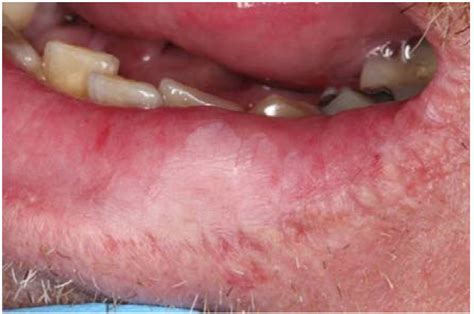

Leukoplakia on the lips is a condition characterized by the appearance of thick, white patches on the lips. These patches are typically painless but can be a cause for concern due to their potential to develop into cancer. Understanding the causes, symptoms, and treatment options for leukoplakia on the lips is crucial for early detection and effective management.

Leukoplakia on the lips refers to the development of white patches or plaques that cannot be scraped off. These patches are usually found on the inner surfaces of the lips and can vary in size and shape. The condition is more common in individuals who smoke or use tobacco products, as well as those who consume excessive amounts of alcohol.

Leukoplakia on the lips often presents with the following symptoms:

• Thick, white patches or plaques on the lips that cannot be scraped off.

• Patches that may be slightly raised or have a rough texture.

• Patches that can be painless or cause discomfort, especially if they become inflamed or infected.

• In some cases, the patches may develop into ulcers or sores.

It is essential to seek medical attention if you notice any white patches on your lips that do not go away within a few weeks. Early detection and treatment of leukoplakia on the lips can prevent the development of more serious conditions, including cancer. Regular dental check-ups and self-examinations can help identify any changes in the mouth and lips.